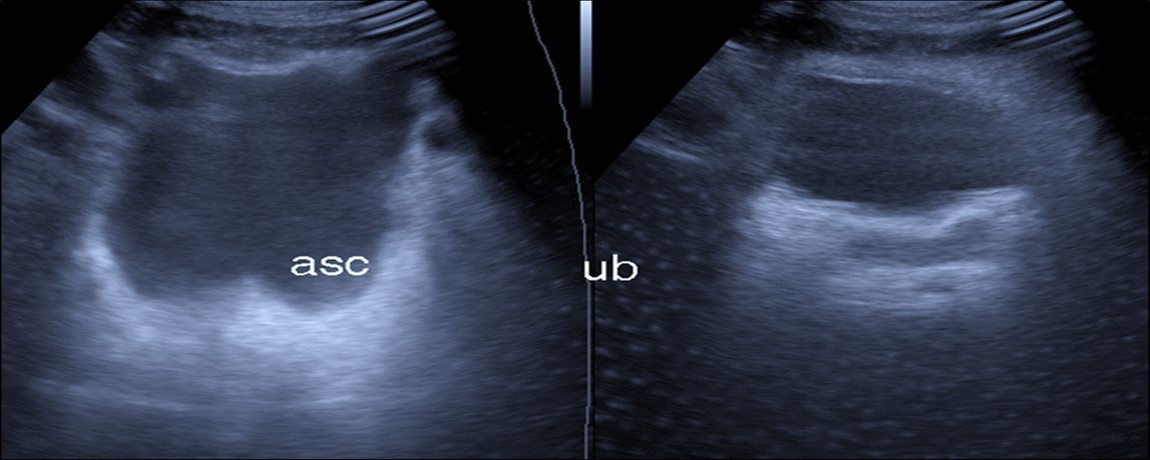

Abdominal ultrasound may revealed any of the followings:-Mild hepatomegaly with echogenic parenchyma and ascites in cases with hepatic impairment (Figure 4, Figure 5) ,thick walls of gall bladder with mildly dilated Common bile duct suggesting of biliary stasis and cholecystitis (Figure 6) .Abnormal renal echogenicity (Figure 7), suprarenal gland enlargements with heterogeneous texture ,splenic wedge shape area of hypoechogenicity ,thickened walls of bowel mainly the rectosigmoid region ,dilated bowel loops with free peritoneal fluid, and gases in the bowel wall with mesenteric and portal vein gases suggesting of bowel wall infarction13.

Figure 6.Real time ultrasound showing free ascites (asc) in patient with Covid-19.

Real time ultrasound showing free ascites (asc) in patient with Covid-19.